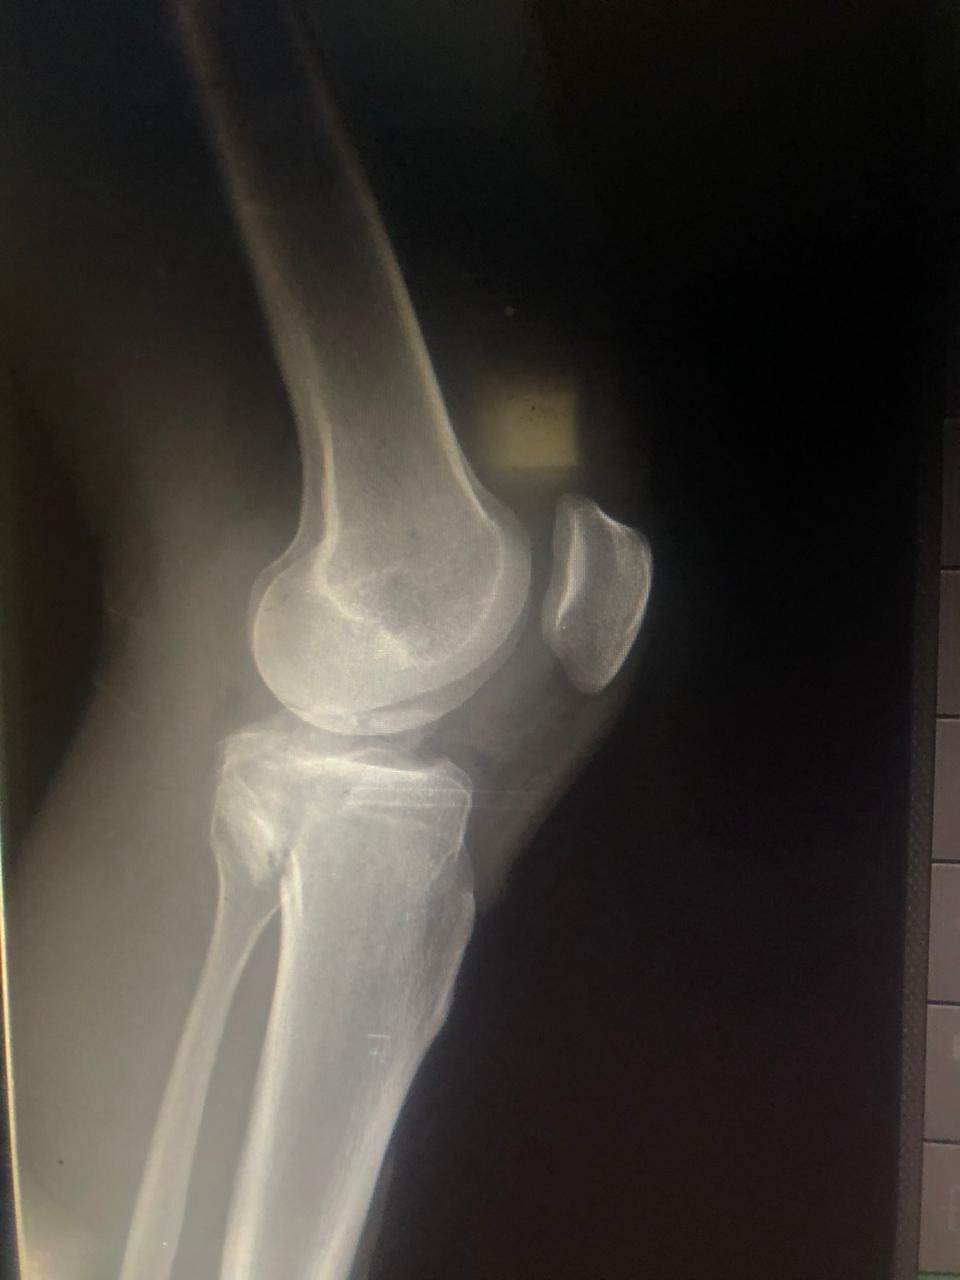

مشيرًا الى أن ذلك النوع من الكسور يكون قريبًا جدًا من الأعصاب والأوعية الدموية الرئيسية للساق والتي توجد خلف مفصل الركبة.. حيث تم الوصول الى الكسر وإعادة بناء سطح المفصل وتثبيته باستخدام شريحة ومسامير وأسلاك معدنية باستخدام جرح ٧ سنتيمترات خلف الركبة واستخدام مسامير جانبية مجوفة بدون فتح لتثبيت الجزء الخارجى من سطح المفصل، وتم الاطمئنان على الأوعية الدموية قبل إفاقة المريض، وبعد تمام الإفاقة.. تم الاطمئنان على الأعصاب والأوعية للمريض.

وأضاف أنه نظرًا لقرب هذا الكسر من سطح المفصل تم عمل أشعة مقطعية بعد الجراحة للتأكد من جودة بناء المفصل وعدم وجود أى بروز للمسامير داخل المفصل، وجارٍ تحضير المريض لعمل رنين مغناطيسى لتحديد الأربطة الداخلية والخارجية للركبة التي ستحتاج لإعادة بناء بالمنظار.